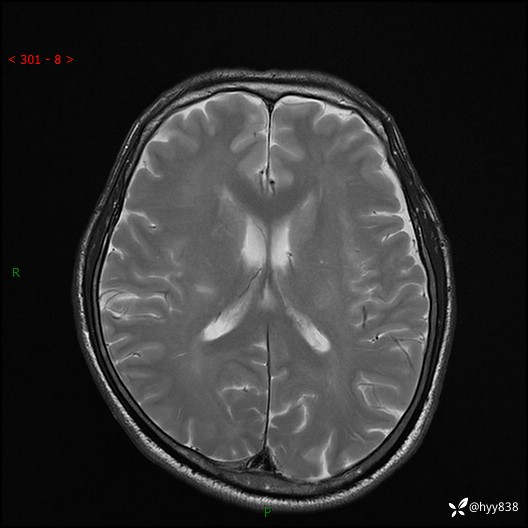

颅脑MRI平扫